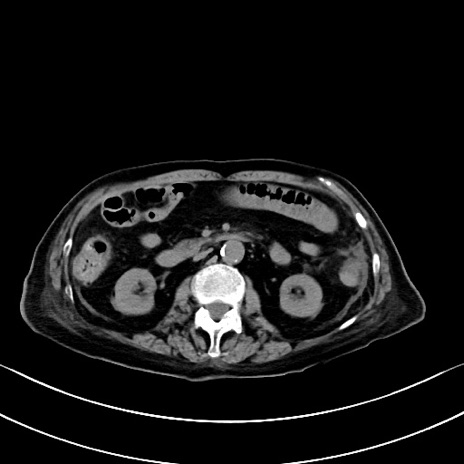

症例40(横断像)他院1日前

横断像

他院CT